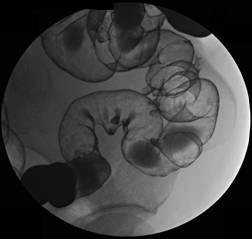

一、什麼是大腸鋇劑檢查(Barium enema)?

大腸鋇劑檢查又稱為下消化道攝影(LGI)。這是針對大腸的特殊X光檢查,包括了直腸、乙狀結腸、下結腸、橫結腸、上結腸、盲腸及闌尾。為使得這些構造能表現在X光片上,將一定量的鋇劑由肛管灌入,然後必須灌入一些空氣進入腸道使其膨脹。

四、檢查方式:

1.檢查時首先請您俯臥在檢查台上,由醫師將肛管插入肛門,醫師灌入適量之顯影劑(鋇劑),並視需要打入適量空氣均勻混合,並依醫師指示於檢查台上做不同姿勢之旋轉。年紀大或行動不便者,最好有家屬陪伴前來或協助攝影‧整個檢查通常需要20~30分鐘。